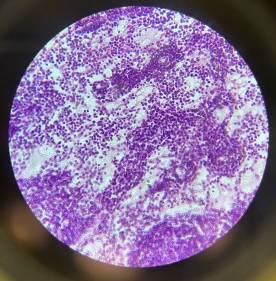

Reticular Connective Tissue (Lymph Node)